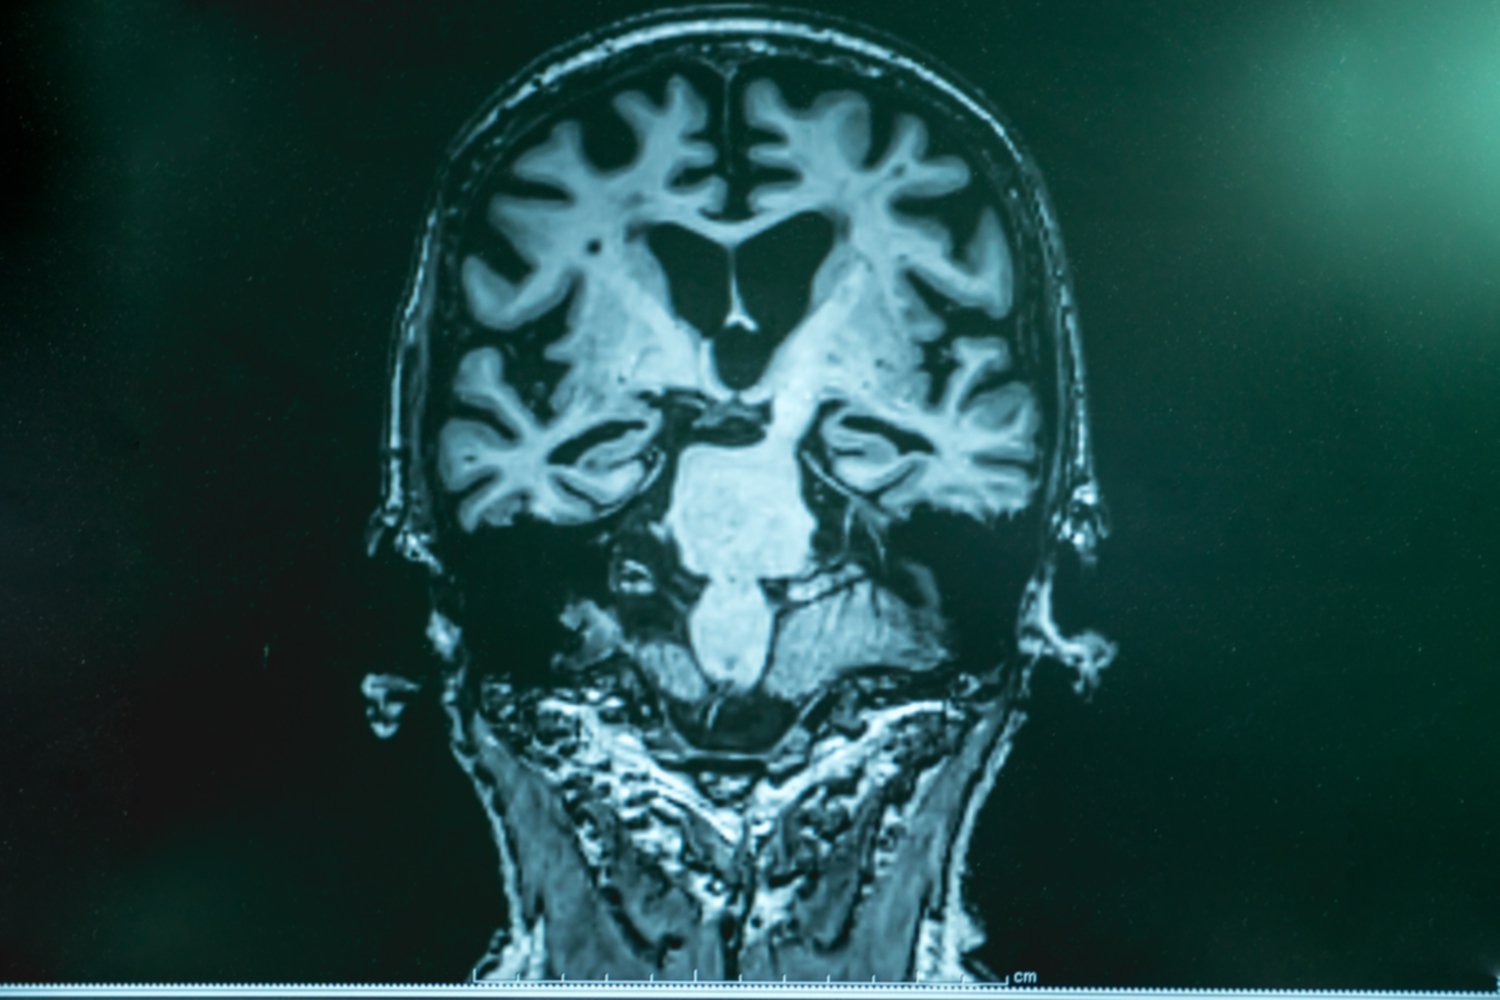

Dementia. Coloured resonance imaging (MRI) scans of the brain Mixed Dementia Brain — mixed dementia is the coexistence of alzheimer's disease and cerebrovascular disease (cvd) in the. — ‘mixed dementia’ is a condition in which a person has more than one type of dementia. The most common is a combination of alzheimer’s disease and vascular dementia. mixed dementia is when you have brain changes from more than one type. Mixed Dementia Brain.